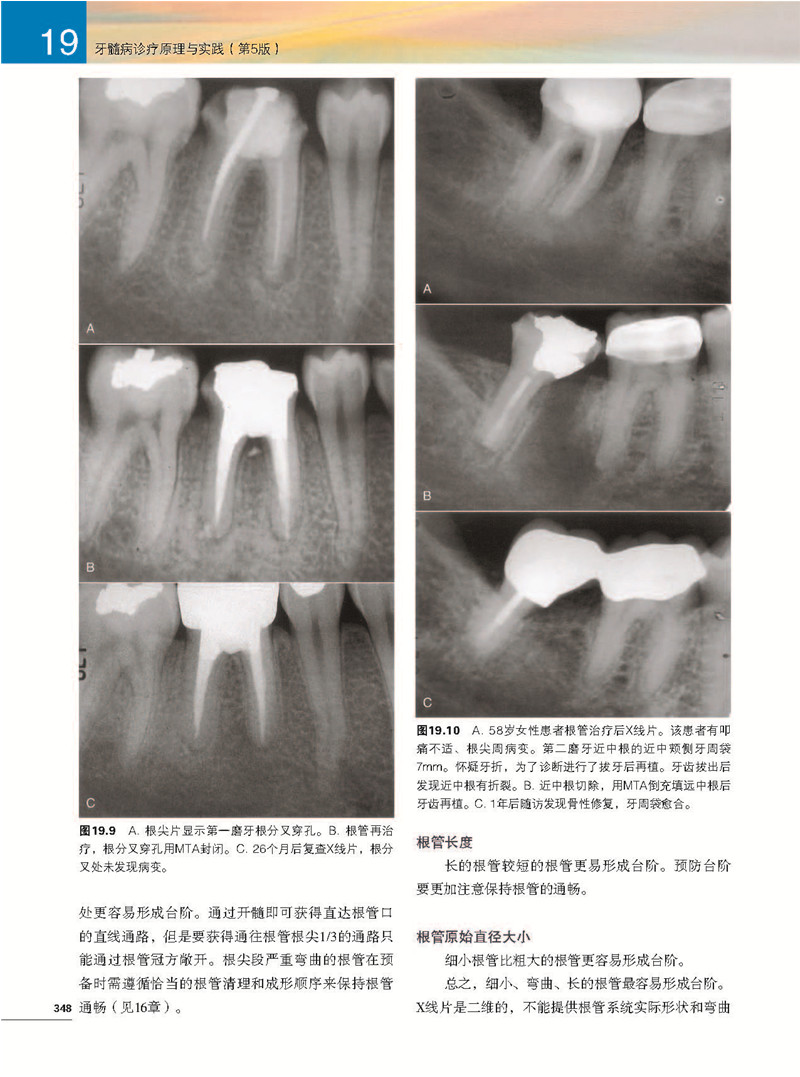

第19章根管治療併發症/ 342

Mahmoud Torabinejad,James D. Johnson